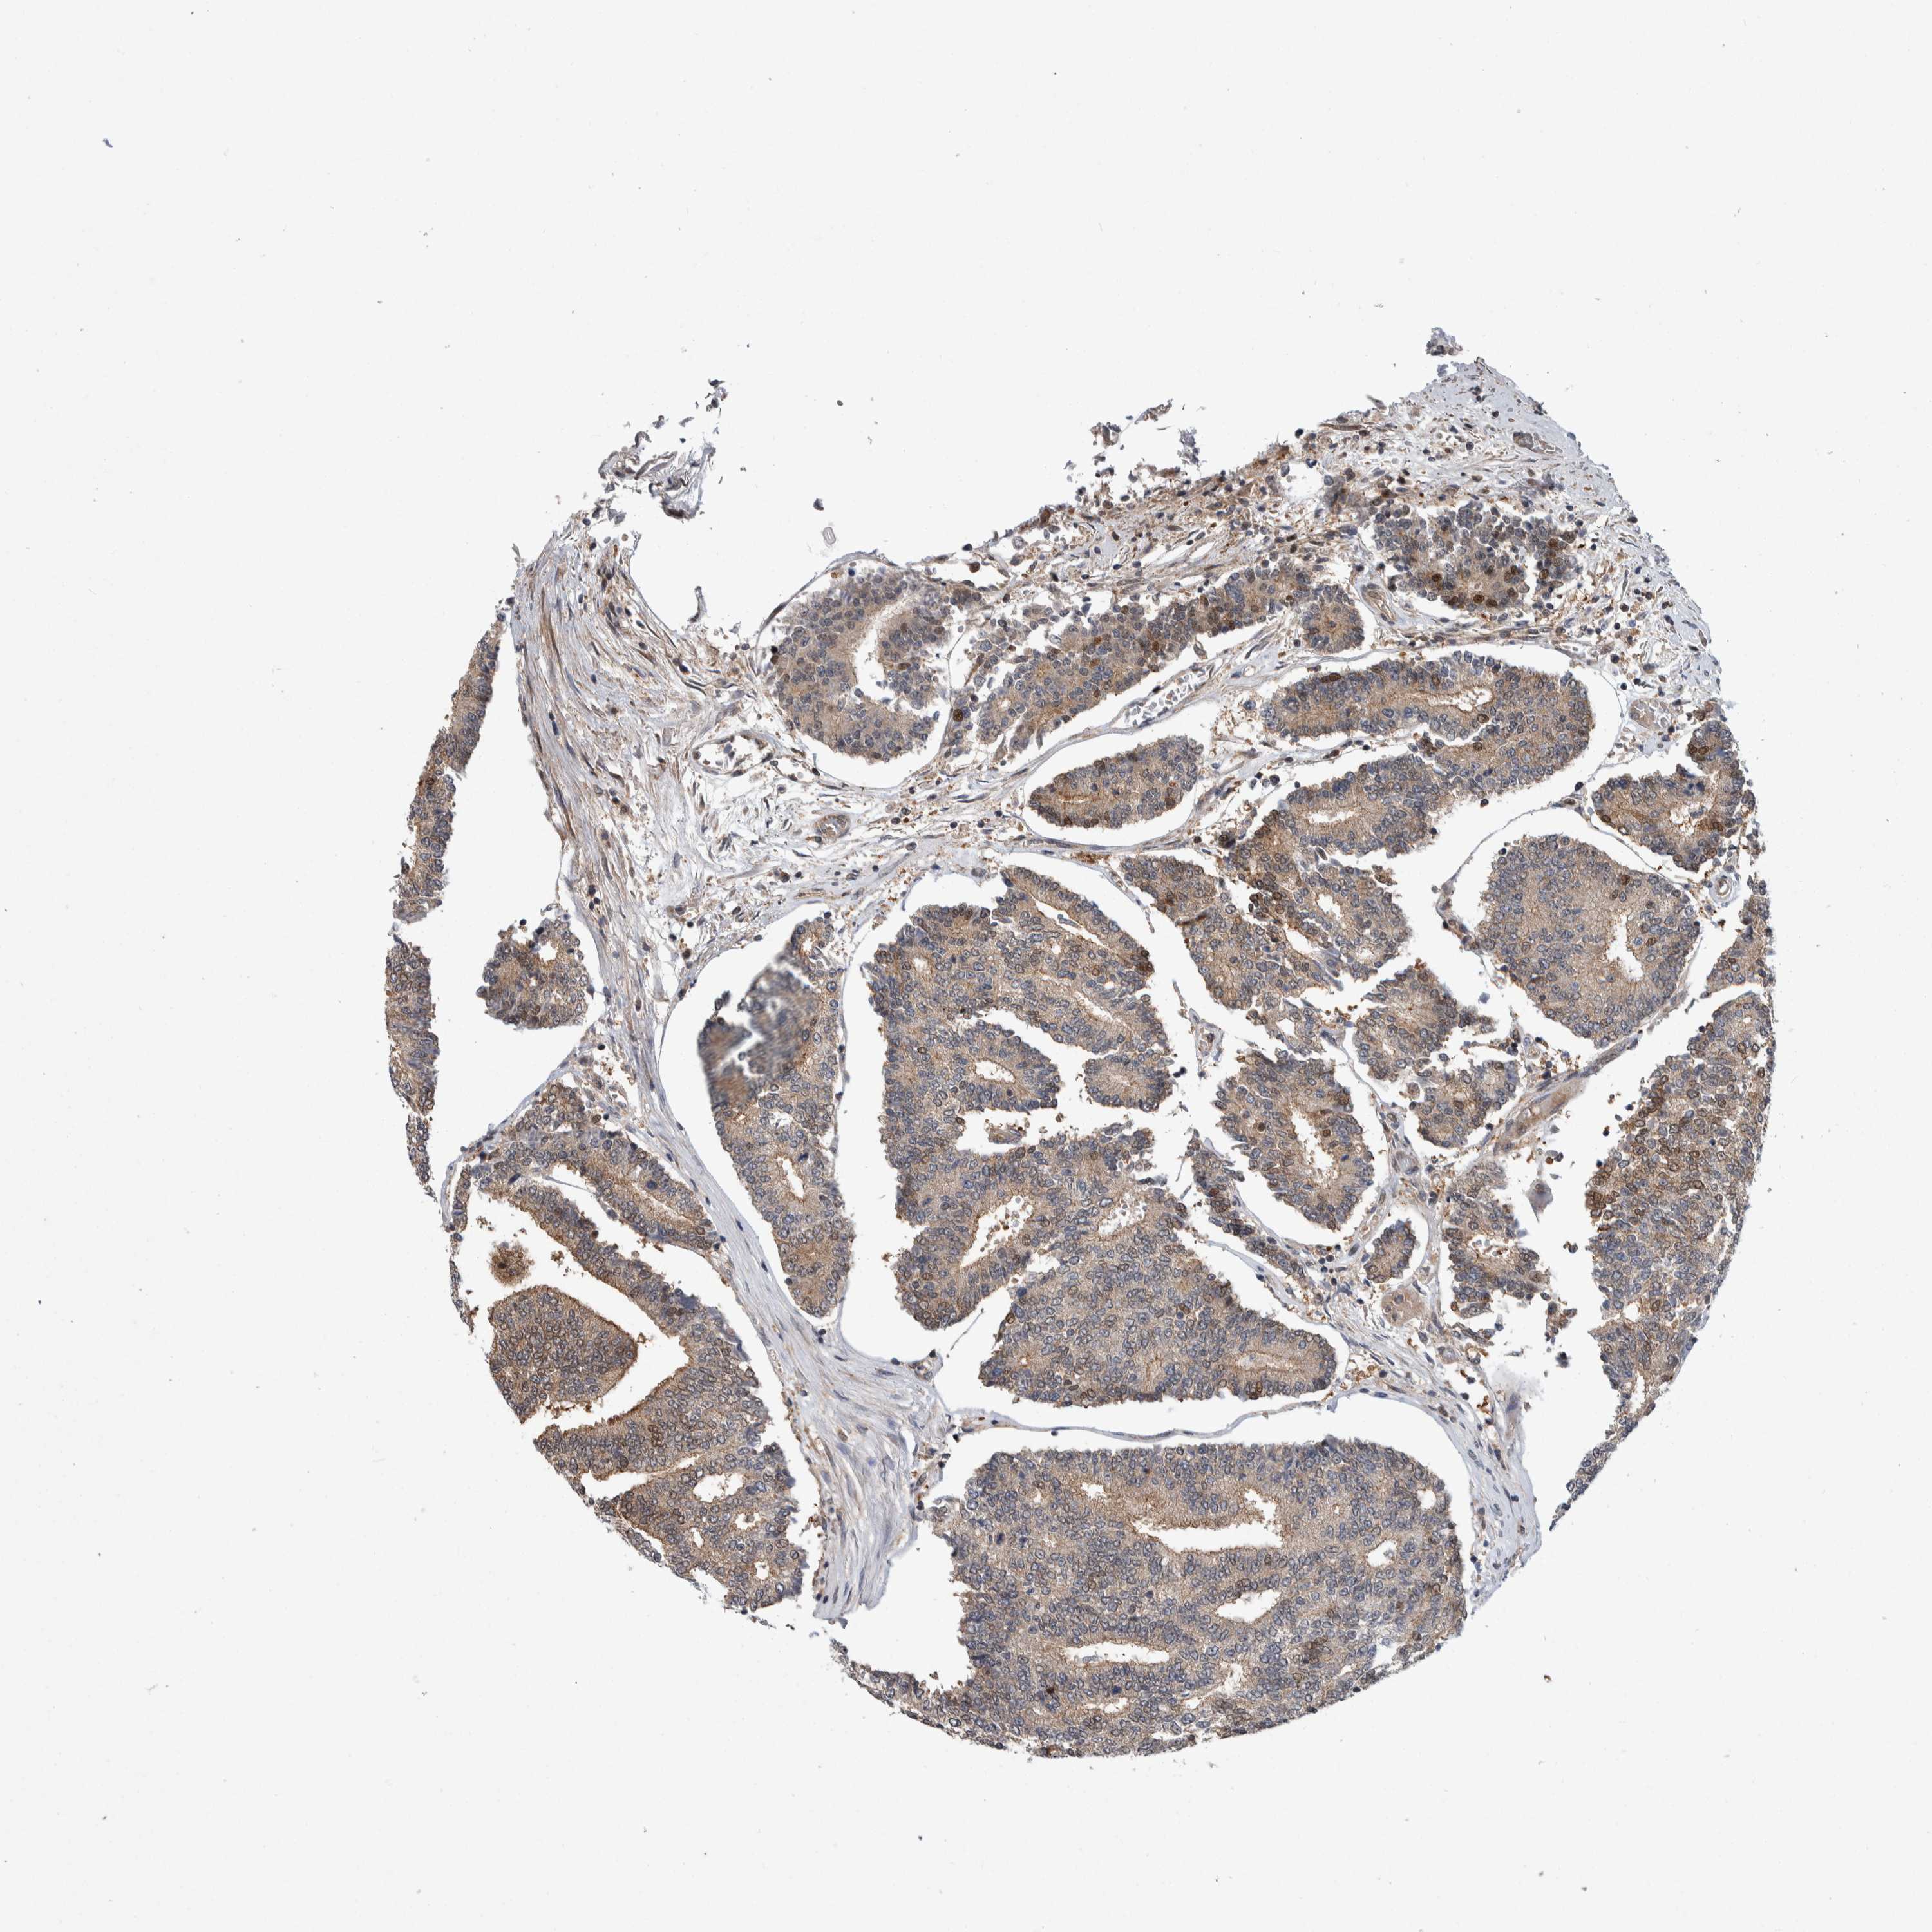

PROSTATE CANCER - Protein expressioni

A mouse-over function shows sample information and annotation data. Click on an image to view it in a full screen mode. Samples can be filtered based on level of antibody staining by selecting one or several of the following categories: high, medium, low and not detected. The assay and annotation is described here.

Note that samples used for immunohistochemistry by the Human Protein Atlas do not correspond to samples in the TCGA dataset.

Antibody stainingi

Antibody staining in the annotated cell types in the current human tissue is reported as not detected, low, medium, or high, based on conventional immunohistochemistry profiling in selected tissues. This score is based on the combination of the staining intensity and fraction of stained cells.

Each image is clickable and will lead to virtual microscopy that enables deeper exploration of all samples and also displays staining intensity scores, fraction scores and subcellular localization as well as patient and tissue information for each sample.

HPA005695

CAB022068

CAB035999

CAB080052

CAB080054

CAB080098

Adenocarcinoma, Low grade

Adenocarcinoma, High grade

Adenocarcinoma, NOS

Adenocarcinoma, Medium grade